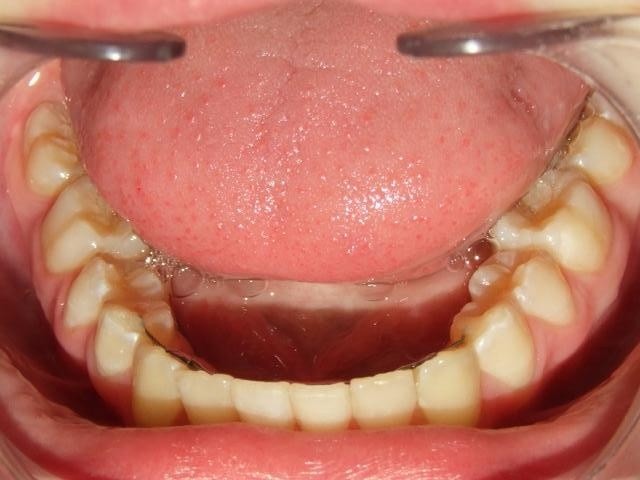

Voor behandeling

Na behandeling